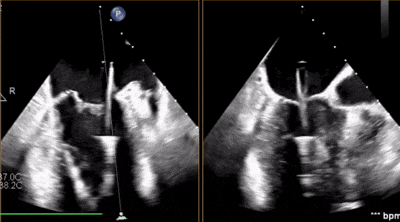

術(shù)前超聲

A3脫垂連枷(脫垂高度9mm,連枷高度:7mm),反流等級(jí)MR 4+(反流寬度11mm),有效瓣環(huán)面積MVA約6.3cm²。前瓣葉長(zhǎng)度23,后瓣葉長(zhǎng)度14.5mm,瓣環(huán)直徑AP 29mm。

術(shù)前術(shù)后對(duì)比

術(shù)前